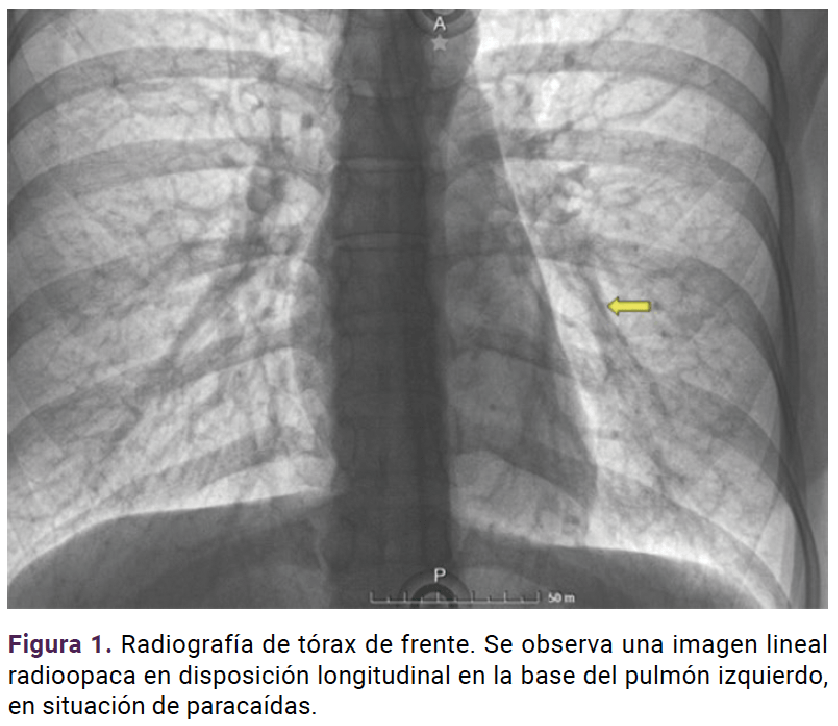

El procedimiento quirúrgico transcurrió sin contratiempos, con la extracción del implante de etonogestrel (Figura 4). La fluoroscopia en tiempo real que evidenció la integridad vascular. La evolución posoperatoria fue favorable y luego del alta hospitalaria ha tenido valoraciones periódicas en la consulta externa sin reporte de alteraciones o molestias.

<strong>Figura 4</strong>

Figura 4